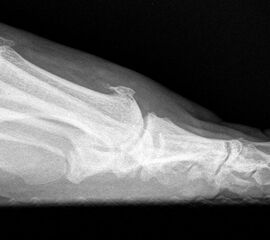

Klinisch zeigt sich stadienabhängig eine schmerzhafte Bewegungseinschränkung mit zunehmender Steifigkeit des Großzehengrundgelenkes. Vor allem die Einschränkung der Dorsalextension wird von den Patienten oft als unangenehm empfunden. Initial besteht eine bindegewebige Alteration im Gelenk, im weiteren Stadium treten Knorpeldegeneration und Begleitsynovialitis mit der Ausbildung von osteophytären Randanbauten auf. Klinische treten diese meist durch eine schmerzhafte dorsale Knochenkante in Erscheinung (Abbildung 1).

Im späten Stadium imponiert eine Gelenkblockierung durch freie Gelenkkörper. Während in den Anfangsstadien vor allem die dorsalen Anteile des Gelenks betroffen sind, betreffen die Veränderungen in den Fortgeschrittenen Stadien die gesamte Zirkumferenz einschließlich des Sesambeingleitlagers. Im Endstadium kommt es zu einer weitgehenden Ankylosierung des 1. Metatarsophalangealgelenks.

Die Cheilektomie ist indiziert vor allem im Stadium II der Erkrankung, in welchem die degenerativen Veränderungen vor allem auf die dorsalen Gelenkanteile konzentriert sind und sich in der plantaren Gelenkhälfte noch ein ausreichender Knorpelbelag findet 48. Der Eingriff umfasst die Synovektomie, die Entfernung von freien Gelenkkörpern und die Abtragung von dorsalen, lateralen und medialen Osteophyten am Metatarsale I Kopf und an der Grundgliedbasis. Zusätzlich kann eine offene Arthrolyse des Sesambeingleitlagers durchgeführt werden. Ziel ist eine Schmerzreduktion durch Abtragung der Ostepohyten mit Verbesserung der Beweglichkeit des 1. Metatarsophalangealgelenkes. Dieses Operationsverfahren kann auch im Stadium III der Erkrankung durchgeführt werden, allerdings ist dann häufiger mit Restbeschwerden und einer signifikant verlängerten Rehabilitationszeit zu rechnen 9.

• Röntgenaufnahme des Fußes in drei Ebenen unter Belastung